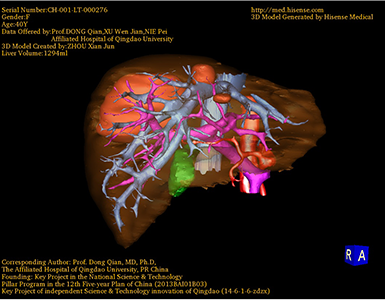

将0.625mm双源薄层CT资料的静脉期和动脉期Dicom格式文件导入海信CAS系统。

通过调节窗宽窗位调整CT序号,对肿瘤,肝实质,胆囊,下腔静脉,肿瘤,肝动脉、门静脉及肝静脉等进行三维重建;系统自动计算肿瘤体积和肝脏体积。

模拟手术操作,自动计算切除肿瘤体积。肝脏体积为1294ml,肿瘤体积为158.5ml,肿瘤体积为肝脏体积的12.2%,通过比对40-50岁正常肝脏体积为1368.38±279.24 ml,通过术前模拟手术,精准判断切除后剩余肝脏体积能耐受,避免肝衰竭发生。

术前三维重建:重建图片